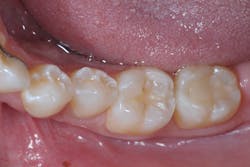

A 27-year-old patient was referred to me due to discomfort associated with dentinal hypersensitivity secondary to erosion on his posterior teeth (figure 1 above: Initial presentation. Note the exposed dentin due to erosion). His former dentist suggested crown lengthening due to inadequate space for full-coverage crowns.

After a thorough evaluation of his clinical presentation, radiographs, and intraoral scan, it was evident that the discomfort was due to exposed dentin. The intraoral scan confirmed there was adequate interocclusal space to restore the eroded tooth structure with a minimally invasive approach (figure 2). All options were reviewed with the patient, and it was mutually agreed upon to address his chief complaint in this manner. Proper isolation is critical for reliable bonding.